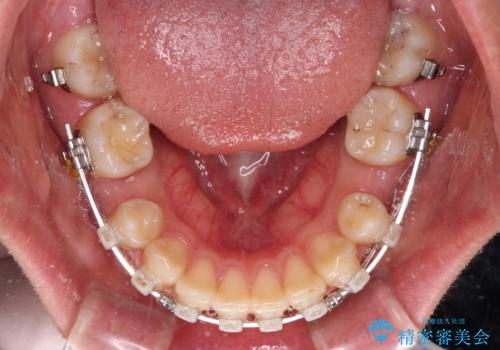

- 矯正装置

- クリアブラケット

口元を極端に引っ込めた印象にしないため、上顎は左右第一小臼歯2本を、下顎は左右第二小臼歯2本を抜歯し、ワイヤー装置にて矯正治療を行うこととしました。

上下の抜歯位置を変えることで、左右ともに理想的な咬み合わせを達成することができました。